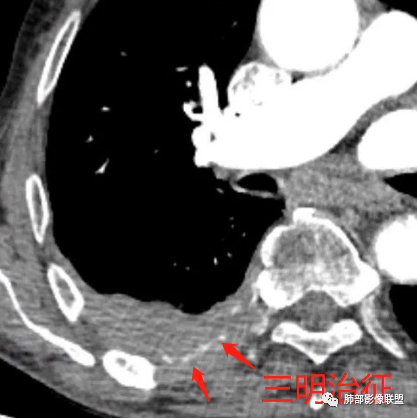

石棉接触史,胸膜三明治征,考虑淋巴瘤,鉴别间皮瘤 医学百科网 | YxBaike.Com

三明治征,应该是典型淋巴瘤

囊,淋巴增殖,三明治,淋巴瘤

肋间动脉漂浮征,淋巴瘤 医学百科网 | YxBaike.Com

黄勇老师讲过,肋间动脉三明治征,淋巴瘤特异性很高。

石棉接触有,却没有胸膜斑。这包的血管是上面老师说的三明治意思 医学百科网 | YxBaike.Com

血管飘浮,三明治,加上纵隔淋巴结多发肿大,部分有融合。基本上定了淋巴瘤了。 医学百科网 | YxBaike.Com

1、老年男性,右侧后胸壁软组织肿块延伸范围较广(至后纵隔主动脉旁),平扫密度均匀稍高,增强扫描均匀强化,其间走行肋间动脉包埋、漂浮(夹心三明治),部分包绕肋骨,肋骨骨质未见明显吸收破坏! 医学百科网 | YxBaike.Com